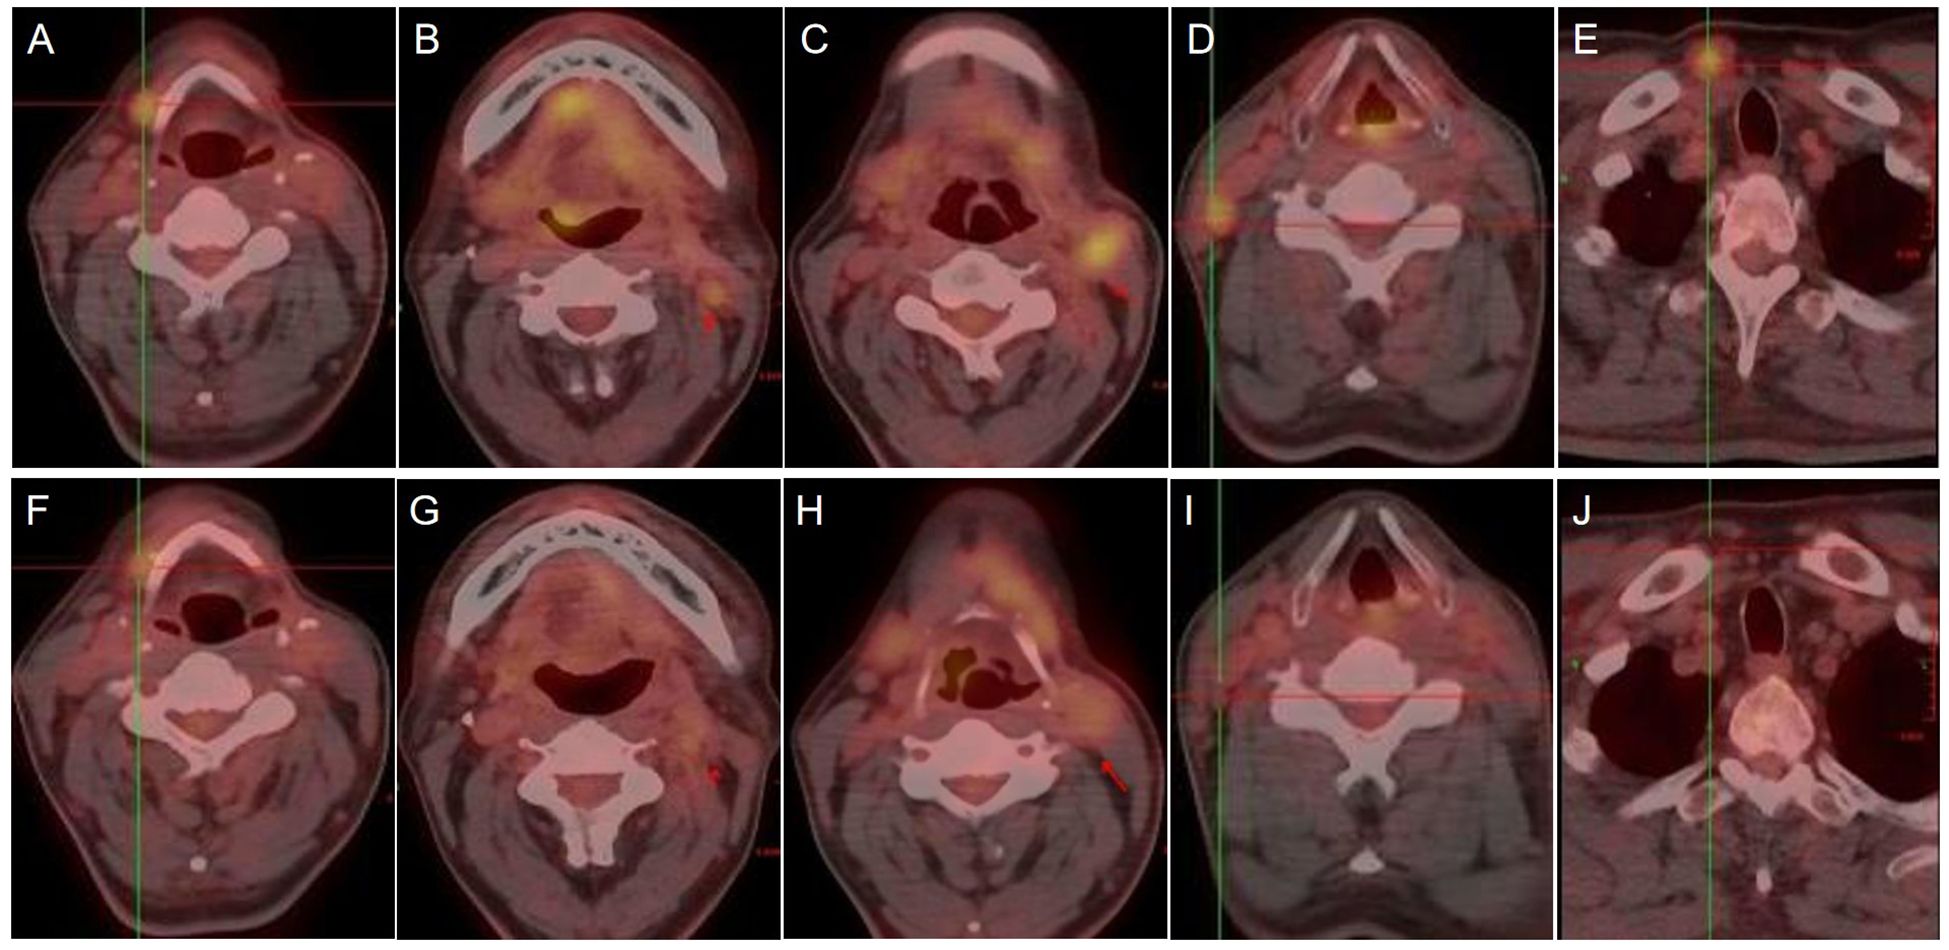

Adenoid Cystic Carcinoma (ACC) is characterized by its aggressive nature, high propensity for perineural invasion, and significant risk of distant metastasis, particularly to the lungs. Therapeutic options for locally advanced or metastatic ACC are limited, and conventional radiotherapy is often constrained by dose limitations for multifocal disease, leading to inadequate treatment. A 54-year-old male ACC patient, who had recurred after three prior surgeries, presented with PET/CT-confirmed bilateral cervical lymph node and multiple bilateral pulmonary metastases. Given the multifocal metastases and the critical need for sparing organs at risk (lungs, heart, esophagus), which rendered photon radiotherapy unable to meet the required dose constraints, proton therapy was employed with the following dose prescriptions: for pulmonary metastases: CTV 50 Gy(RBE) in 15 fractions, GTV 60 Gy(RBE) in 15 fractions; for the cervical lesion: GTVnd 70 Gy(RBE) in 28 fractions, CTVnd 66 Gy(RBE) in 28 fractions, CTV 50.4 Gy(RBE) in 28 fractions. Follow-up PET/CT post-treatment demonstrated complete resolution of some bilateral pulmonary metastases, with marked reduction in size and decreased metabolism in the remaining nodules. The metastatic cervical lymph nodes also showed reduced volume and metabolic activity. No adverse events exceeding Grade 2 occurred during the treatment course. This case demonstrates that proton therapy is highly suitable for multifocal ACC metastases, especially multiple small pulmonary nodules. Through its precise dose delivery, it enables high-dose irradiation (GTV 60–70 Gy(RBE)) to targets while significantly sparing normal organs. This approach represents a viable strategy for complex cases where conventional radiotherapy is contraindicated. It aims to delay disease progression and achieve organ preservation in refractory ACC.